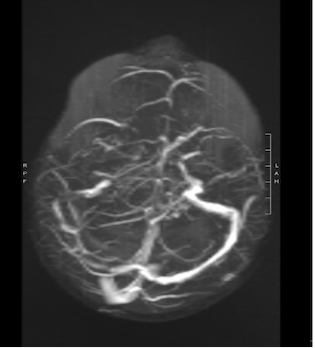

In considerazione della storia clinica, i bambini venivano sottoposti a RM che evidenziava in entrambi i casi un quadro di trombosi venosa cerebrale, con estensione nel primo caso al seno trasverso, sigmoideo e bulbo della giugulare destro, in associazione alla presenza di segni di flogosi a carico delle cellette mastoidee (Figura 1), mentre nel secondo caso trombosi subacuta con coinvolgimento di seno trasverso, sigmoideo, bulbo, tratto craniale della giugulare interna e sospetto iniziale impegno della vena di Labbé a sinistra, senza flogosi mastoidea (Figura 2).